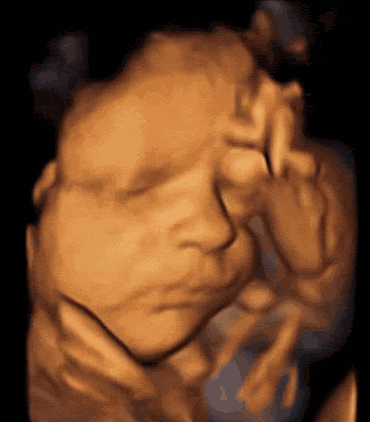

福兴妇产医院是泉州地区较早引进具有“神器彩超”之称的美囯GE四维彩超的医院。美囯GE系列四维彩超以出色的成像技能、自动化辅助诊断工具、更高的硬件性能被广大孕妈和医生信赖。四维彩超能够、多角度动态显示未出生的宝宝的活动图像和人体内脏器官的图像。>>>宝宝在肚子里怎么会动?我也要一组这样的“0”岁写真